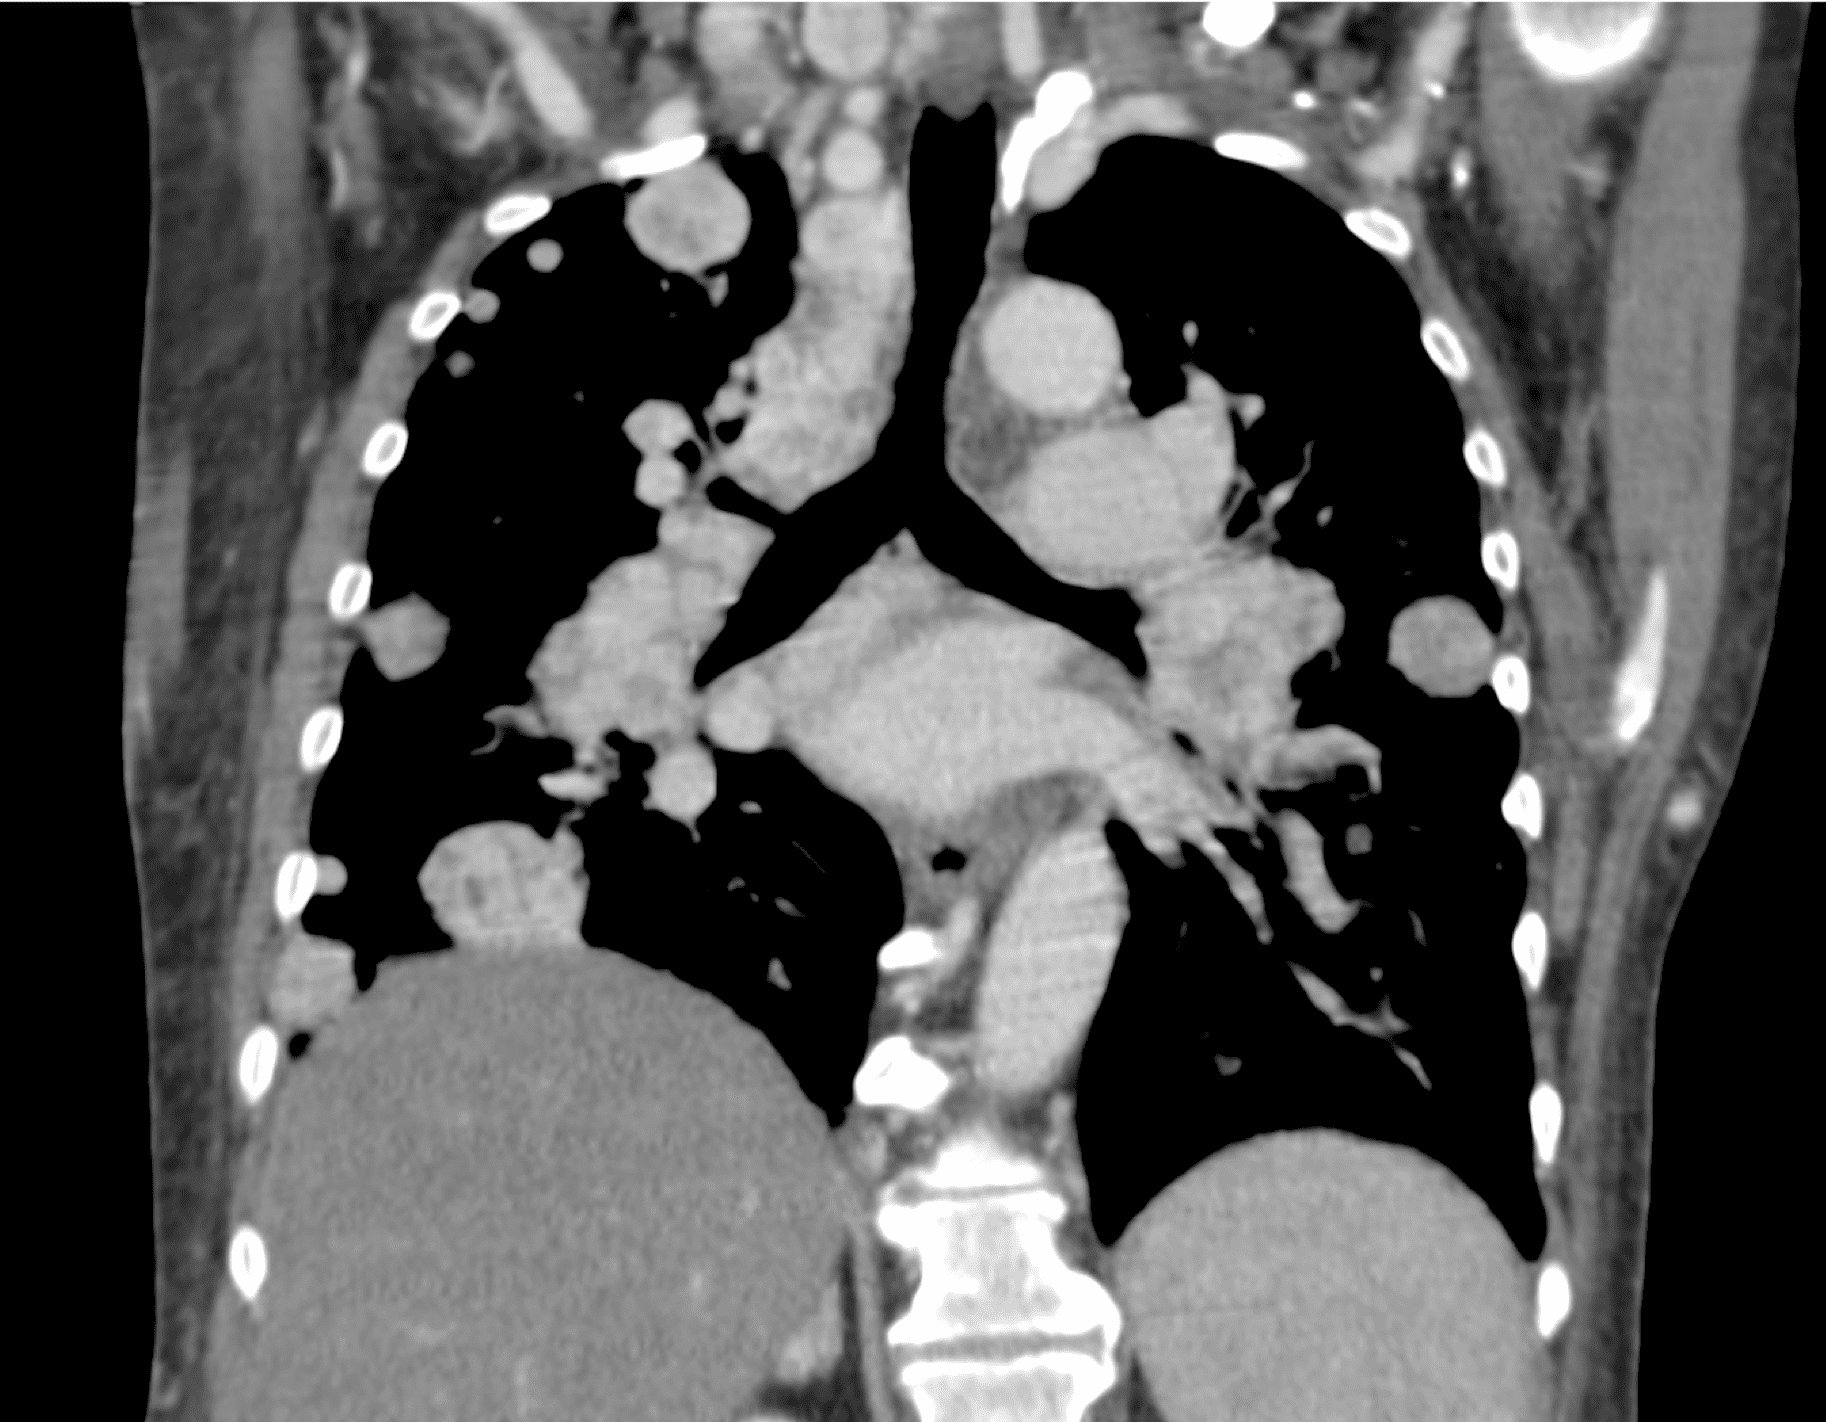

Рентгеновские снимки тератомы средостения: Диагностика и лечение

Раздел: Фотоэссе